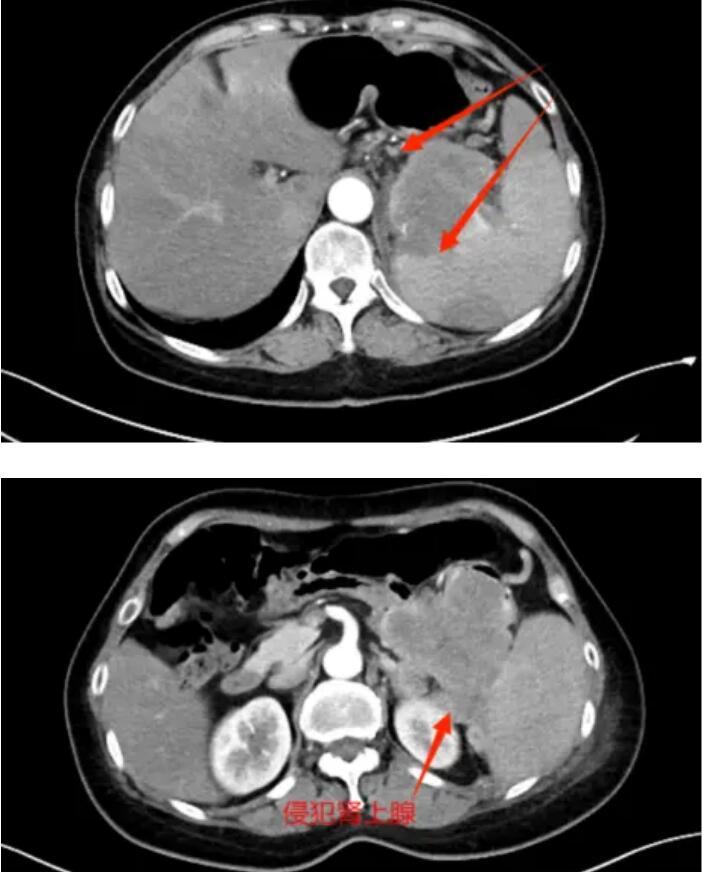

年过六旬的赵大娘(化名)近一月以来间断性出现左下腹疼痛,每次发作呈刺痛,伴食欲减退,排便困难,症状持续加重,门诊查CT回报:左上腹结肠占位性病变,考虑恶性,左肾上腺占位,考虑转移瘤可能(径线34mm*17mm),胃肠镜检查提示:“结肠肿物,结肠黏膜隆起”。赵女士家属拿到检查报告后心急如焚,经多方打听后,赵大娘来到了胃胰脾外科,希望得到救治。翟博教授经评估了患者影像资料后,考虑患者为胰腺体尾部的恶性肿瘤,并累及周围脏器。入院后的增强CT证实了上述诊断。

肿瘤侵犯脾及结肠、肾上腺

肿瘤侵犯结肠,肠管受压,造成患者排气排便困难

由于患者瘤体巨大,侵及周围脾、肾上腺、结肠、胃、十二指肠等多个脏器器官,手术难度极高,翟博教授随即请科室主任谭刚教授会诊,基于对患者病情分析及为降低手术风险,完善胰腺三维成像,得以精准定位肿瘤位置及周围血管分布,精准规划手术流程。

谭刚教授仔细研究了赵大娘的病情,认为肿瘤虽然涉及多个脏器,但尚未发生远处转移,为挽救患者生命,谭刚教授毅然决定开腹探查,以期为患者争取最后的治疗机会,经过周密的术前准备,赵大娘躺到了手术台上。术中探查可见胰体尾肿物,累及脾门、侵及结肠脾曲,脾动静脉、胃底及十二指肠,在谭刚教授、翟博教授两位主任的精密合作下,经过3个多小时的艰苦奋战,为赵大娘施行了“根治性胰体尾切除、脾切除、结肠脾曲切除、胃十二指肠修补术,左侧肾上腺切除”的多器官联合切除,患者术后顺利返回病房。目前患者恢复非常顺利,已康复出院。出院时,赵大娘家属激动地表示:“真的没想到这么大的肿瘤还有根治的希望,在切除了这么多器官后,术后还恢复得这么快,感谢普外二团队给了我老伴第二次生命!”。